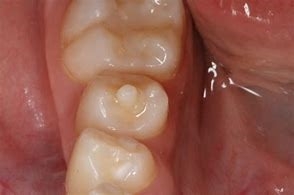

次に基底結節、中心結節の形態異常です。

これは歯の一部が円錐状の棘のように突き出した形態をしているものです。

これらは前歯や奥歯(第一、二小臼歯)に出現するためご本人も気づかないことが多いです。

しかし、この棘(とげ)のようなところにも神経(歯髄)が伸びていて

食事などで折れてしまうと突然虫歯のような神経の痛みが出たり

また知らない間に神経に感染して神経が死んでしまうことがあります。

棘が細長く折れてしまうようなリスクのある方は、虫歯の治療で詰める

ようなプラスチックであらかじめ補強することが出来ます。